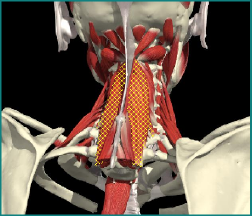

RETROCOLLIS- ATTACH TO NECK

Midline -attach to spine

- Semispinalis cervicis

- Longissimus cervicis

Range of Motion

- 66 degrees